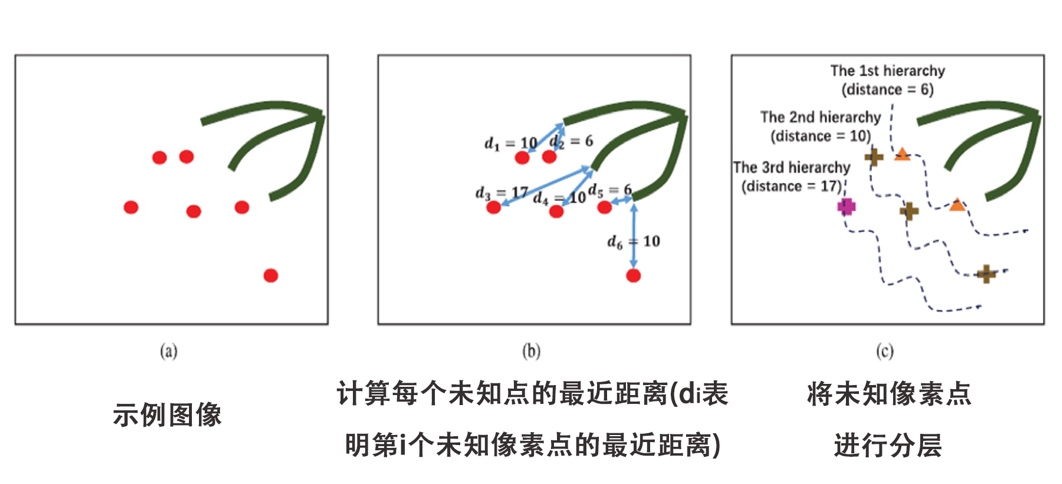

图三 分层抠图模型的算法框架和实例展示 图四和图五分别展示了分层抠图模型算法中两个步骤的基本流程,其中绿色代表血管点,红色代表未知点,蓝色代表背景点。在第一步对未知像素点的分层过程中,我们计算每个未知像素点与最近血管点的距离,并按该距离将未知点分层。在第二步分层更新过程中,从第一层开始,我们计算该层每个未知像素点和它最近的已知点(血管点和背景点)的关系值,选择每个未知像素点关系最近的已知点,把这个已知点的标记赋给未知的像素点。当该层所有的未知像素点更新后,我们再用它们继续对下一层的未知像素点进行更新,以此循环,直到最后一层更新完毕。

图四 未知像素点的分层示例流程图